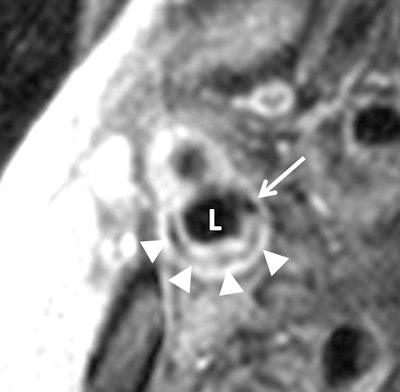

Previous research has shown that some arterial plaque is more dangerous because of its vulnerability to rupture. MRI can discern features of this vulnerable plaque, such as a lipid core with a thin fibrous cap, making MRI potentially valuable for identifying patients at risk for future cardiovascular events.

Zavodni's group used ultrasound to assess carotid wall thickness and MRI to define carotid plaque composition and remodeling index, a measure of changes in vessel size, in 946 asymptomatic patients from MESA. Each MESA center used a 1.5-tesla MRI scanner and dedicated carotid coils to obtain images of the carotid arteries.

"One of the more histological components seems to be this lipid core," he explained. "In the area of the artery's thick wall, if the wall erodes, it exposes lipid core to the bloodstream and a clot will form. In a large vessel, such as the carotid artery, that clot can potentially break off, go to the brain, and cause a stroke."

Cardiovascular events occurred in 59 subjects (6%), the researchers found. Carotid intima-media thickness as determined by ultrasound and remodeling index, lipid core, and calcium in the internal carotid artery on MRI were all significant predictors of cardiovascular events in univariate analysis.

A lipid core was present in almost half of the patients who had an adverse event, compared with only 17.8% of participants who did not have an event, according to Zavodni and colleagues.